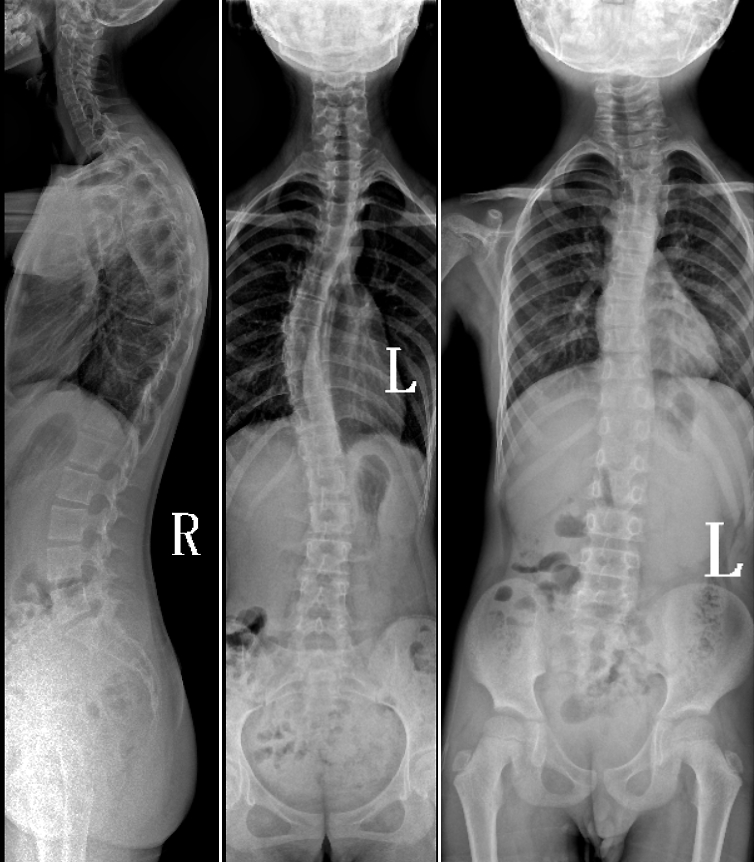

DR是臨床骨科的重要檢查手段之一。在骨科檢查中,脊柱矯形、長骨骨折、腰椎退行性病變等,需要采集脊柱、下肢全景圖像,輔助醫(yī)生臨床診斷,從而制定科學(xué)的治療方案,普愛醫(yī)療的大視野平板動態(tài)DR就像是一座橋梁,連接起現(xiàn)代醫(yī)療技術(shù)與當?shù)厝嗣竦尼t(yī)療需求。

普愛醫(yī)療自主研發(fā)的大視野平板動態(tài),采用17"*34"的有效視野,一次曝光即可得到全脊柱或全下肢影像。相較于多張攝影再軟件拼接的DR設(shè)備,PLX8600解決了拼接圖像存在密度不均勻,拼接處圖像配準和放大效應(yīng)等問題,給臨床帶來了真正的大視野影像解決方案。

除了常規(guī)靜態(tài)攝影外,PLX8600的大平板具備動態(tài)透視和點片功能,能夠很好地觀察復(fù)雜部位病灶,有效地抓取關(guān)鍵幀,降低患者多次攝片的概率。如:全脊柱狀態(tài)評估、長骨關(guān)節(jié)活動度、下肢靜脈造影瓣膜功能評估、消化道功能評估、脊髓造影等更多大視野臨床應(yīng)用,“多面手”都能輕松應(yīng)對。